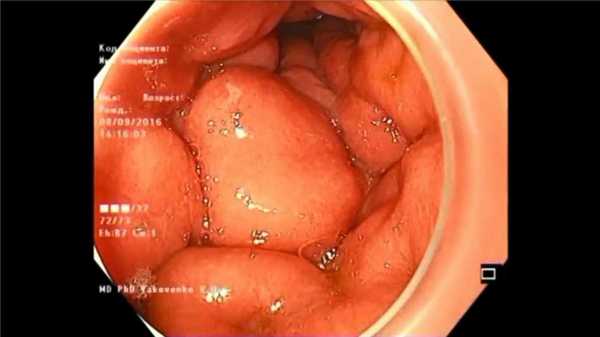

сужение антрального отдела желудка, утолщенные плотные желудочные складки и воспалительный отёк слизистой оболочки желудка